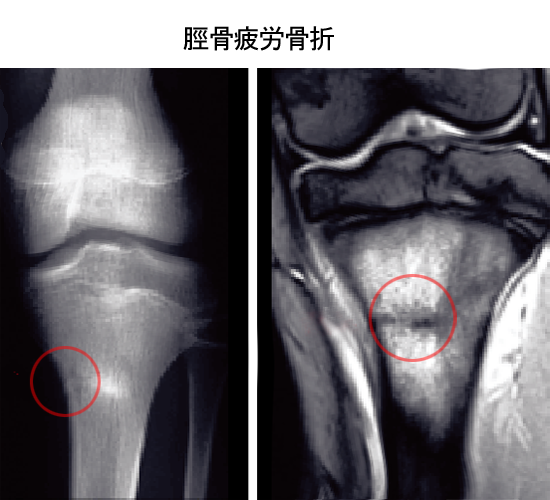

中長距離選手が悩まされる疾患に脛骨、腓骨、中足骨の疲労性骨折があります。

私の原因論は膝の半月板の亜脱臼が疲労性骨折に深く関与していると考えております。

疲労性骨折がひざ半月板に関与している事実はまだ医学界では知られておりません。